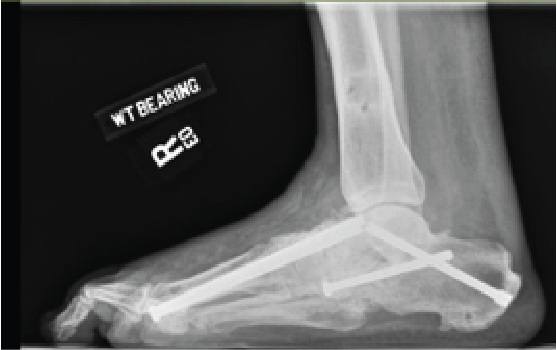

Developing a surgical plan includes identifying the Charcot stage and location (as more proximal Charcot leads to a worse prognostic outcome with respect to deformity and ulceration). Follow this with deformity planning, staging the procedure as indicated and subsequently determining the fixation strategy. The ultimate goal of Charcot reconstruction is a solid construct that puts the patient at decreased risk for further breakdown with a foot that is able to bear weight in a shoe or brace with stable hindfoot alignment. Important principles for reconstruction are to align the heel under the mechanical axis of the lower leg with passive dorsiflexion of 5 degrees past neutral and the metatarsal heads perpendicular to the heel with weight evenly distributed.27 It is important to stabilize the adjacent joints and incorporate the use of orthobiologics in areas where bone quality or deformity require additional support.

Hindfoot stability through fusion has proven successful in Charcot deformity correction with the incorporation of retrograde intramedullary nail fixation. Studies have indicated that intramedullary nail fixation interferes with endosteal blood flow initially but patients subsequently have complete restoration after three weeks in the absence of reaming and complete restoration in six weeks if reaming occurred.33 Typical indications for external fixation are when the patient is not amenable to casting, the deformity cannot have acute correction, evidence or suspicion for osteomyelitis, localized soft tissue infection, or when there is inadequate bone for internal fixation.34

In our experience, a useful indication for external fixation is in the setting of significant concomitant ankle and subtalar joint Charcot in which the calcaneal substrate becomes denuded and is not a stable foundation for intramedullary nail fixation. Many surgeons prefer a combination of intramedullary nail fixation with adjunctive external fixation. Researchers have proven that a combination of internal intramedullary nailing with supplemental external ring fixation has not decreased limb salvage rates.35 The literature seems to support that intramedullary nail fixation leads to higher rates of union but more revision surgery and complications whereas external fixation commonly incurs pin site complications.36,37